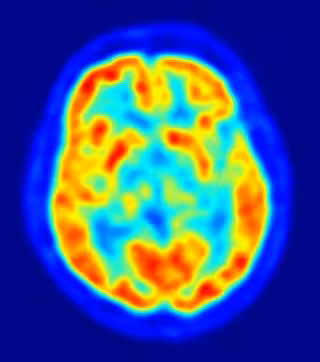

Se ha descubierto que el zinc desempeña un papel crítico en la regulación de la comunicación entre las células del cerebro que rigen la formación de los recuerdos y controlan la aparición de crisis epilépticas.

Los investigadores de un proyecto de colaboración entre el Centro Médico de la Universidad de Duke en Durham y químicos del Instituto de Tecnología de Massachusetts, ambos en Estados Unidos, han sido capaces de observar el zinc en acción mientras regulaba la comunicación entre las neuronas del hipocampo -- donde se producen los procesos de aprendizaje y memoria y donde una perturbación de la comunicación puede contribuir a la epilepsia. El estudio ha sido publicado en la revista 'Neuron'.

Hace más de 50 años los científicos descubrieron altas concentraciones de zinc en unos compartimentos especializados de las células nerviosas, llamados vesículas, que contienen los transmisores que permiten a las células nerviosas comunicarse. Las mayores concentraciones de zinc del cerebro se encuentran entre las neuronas del hipocampo, el centro de aprendizaje y la memoria; la presencia de zinc en estas vesículas sugiere que éste juega un papel en la comunicación entre las células nerviosas, pero se desconocía cuál.

Las células nerviosas donde residen altas concentraciones de zinc son fundamentales para un tipo particular de formación de la memoria. Un aumento excesivo de la comunicación de las células nerviosas que contienen zinc produce y empeora la epilepsia. "Controlar cuidadosamente la regulación de zinc entre estas células nerviosas es esencial tanto para el control de la formación de recuerdos como para el control de la aparición de las crisis epilépticas", afirma McNamara.